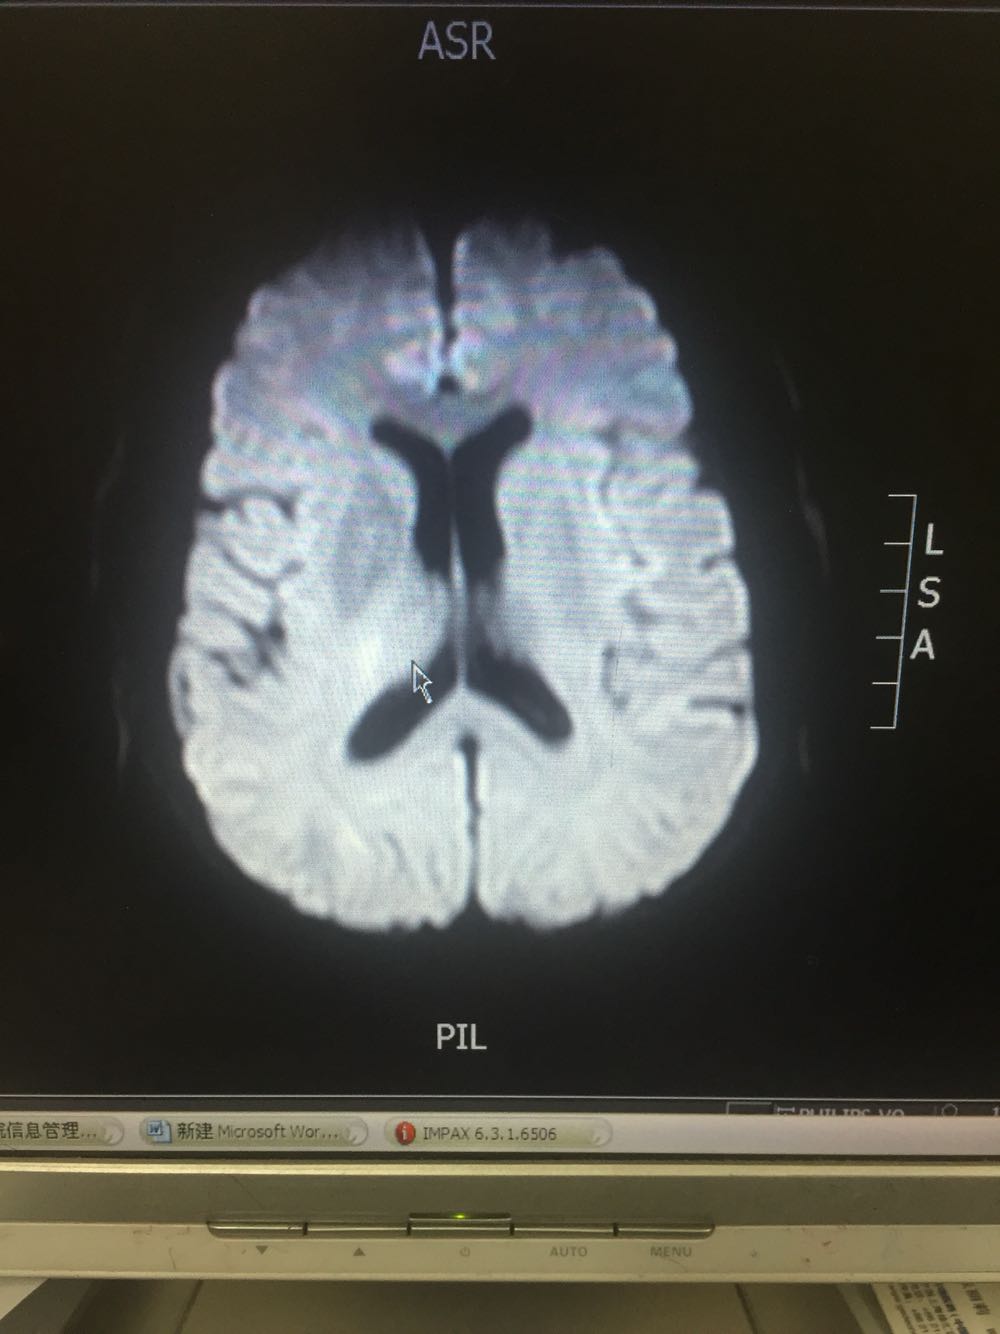

患者于入院后第二日晨起时突发左侧肢体无力伴抽搐发作,查体:神志模糊,言语含糊,双侧瞳孔等大同圆,对光发射存在,左侧肢体肌力3级,左下肢Babinski(+)Chaddock(+) 不伴有尿便失禁。给予安定肌肉注射,急检血凝及头CT。血凝、头CT回报未见明显异常。患者发病1.5小时与家属沟通建议溶栓治疗,家属同意。患者体重约75kg。给予6mg爱通立静脉推注,随后60分钟内爱通立54mg静脉滴注。患者恢复良好,肌力恢复正常。查头DWI示:右侧侧脑室后脚可疑新发梗死。